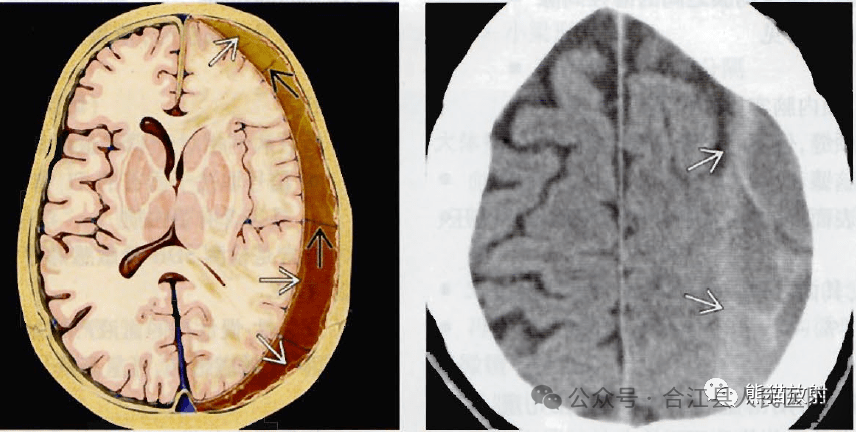

图片

慢性硬膜下血肿解剖图及CT表现